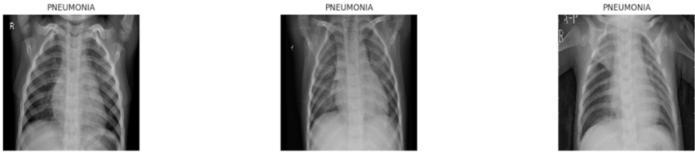

Theefficacyofadeeplearningsystemisinextricablylinked tothequalityandorganizationofitsinputdata.Theproject utilizesawell-curateddatasetconsistingoflabelledchestXrayimages,sourcedtypicallyfrompublicarchivessuchas Kaggle’s Chest X-ray dataset or the National Institutes of Health(NIH)dataset.1 Thisdatasetispartitionedintothree distinctsets:Training,Validation,andTest,ensuringthatthe final performance evaluation is conducted on completely unseendata.

A critical challenge in medical datasets, particularly for binary classification like pneumonia detection, is class imbalance. The following table provides a hypothetical representationofthelikelydistribution,illustratingahigh imbalancewherepneumoniacasessignificantlyoutnumber normalcases,especiallyinthetrainingset,whichiscommon inclinicaldatacollection.

Tostandardizethevisualinputsandoptimizethemfordeep learning, all images undergo a rigorous preprocessing pipeline. Standardization involves resizing all images to a uniformdimension,specifically224*224pixels,whichisthe required input size for the classification backbones (ResNet50andDenseNet121).Additionally,pixelintensity values are normalized to the range to ensure consistency across the dataset, which improves model convergence speedandstability.

Data augmentation is exclusively applied to the training dataset to enhance model robustness and prevent overfitting. This involves applying geometric and photometric transformations designed to simulate the variationsencounteredinreal-worldclinicalsettings,such as slight positioning differences or variations in imaging quality.Specifictransformationsincluderotation(upto10 Degree),shiftsinwidthandheight(upto6%),zoom(upto 8%),andhorizontalflipping.